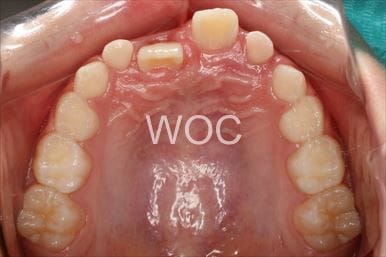

八重歯・叢生上のみ舌側矯正、下はエッジワイズ装置

上は舌側矯正を希望。ガタガタ(叢生)が強い。上顎右側中切歯・側切歯が歯科治療で連結してあったがそれを除去してから治療開始しました。

- 年齢:23歳女性

- 主訴:上下前歯のガタガタが気になる

- 基本矯正料金:103万円

- 治療期間:2年2ヶ月

- 非抜歯